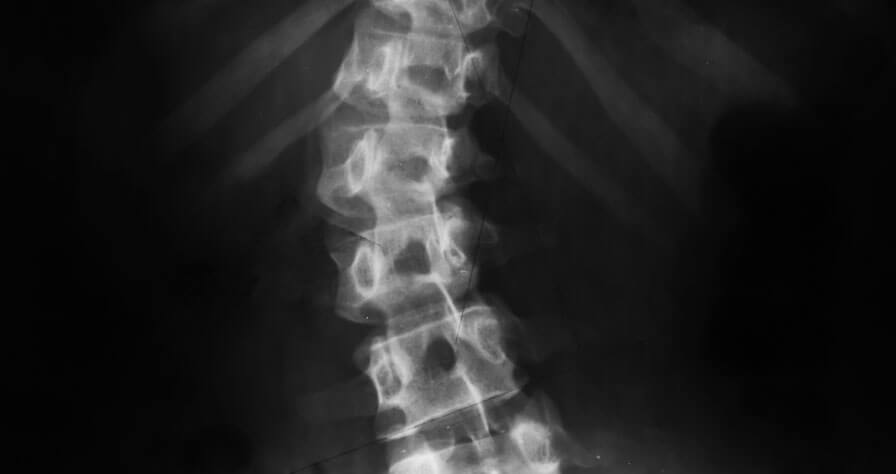

SMA (spinal muscular atrophy) is an inherited disease that most often affects the muscles of babies and children – taking away their ability to walk, eat or breathe. It is the number one genetic cause of death for infants.